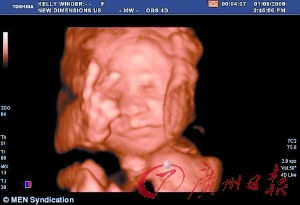

宝宝的器官已经完全发育,并各就其位了。宝宝现在可能重2.7~3.4千克,长48.3~50.8厘米,像一个西瓜那么大了。他的抓握已经很有力了,很快你就会在他的小手抓住你的手指时注意到这一点!